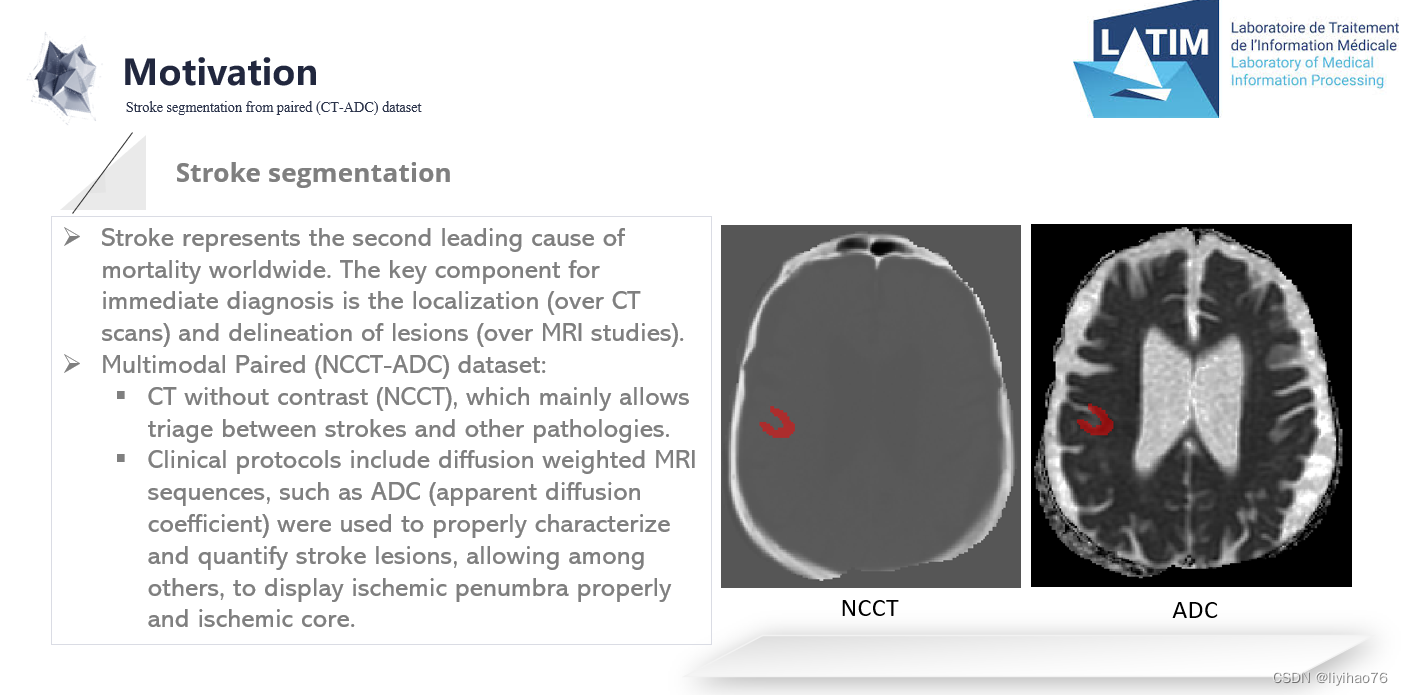

中风是全球第二大死亡原因。 即时诊断的关键组成部分是定位(通过 CT 扫描)和病变描绘(通过 MRI 研究)。 尽管如此,病灶的描绘仍然很差,仅在晚期可见,并且分析使用手动描绘。 这个挑战引入了 CT 和 ADC 研究的配对数据集。 邀请研究人员提出计算策略,在训练期间处理配对数据,并处理 CT 起始序列上的病变分割。 在培训期间,将提供带注释的配对序列(来自一位专家),并且将针对两位专家比较用于测试的结果分割。

CT (NCCT) 主要允许对中风和其他病理进行分类。 然而,此类序列对缺血的对比度差、敏感性和特异性低,并且病变的低衰减具有时间依赖性。因此,临床方案包括扩散加权 MRI 序列,例如 ADC(表观扩散系数),以正确描述和量化中风病变,除其他外,允许正确显示缺血半影和缺血核心。APIS 挑战赛提供配对 (CT-ADC) 数据集。 有 60 个成对的 (CT-ADC) 数据集以及来自专业放射科医师的相关描述以供训练。 最后将使用40个数据集作为测试集进行验证

- NCCT

-NCCT 可用于区分缺血和出血并检测早期缺血变化 [3]。

-它的快速获取和高可用性与诊断中风有关。

-在最初几个小时内,细微的低衰减是中风的预测因素,但其对比度差导致检测缺血的灵敏度和特异性较低。

- ADC

-这种成像技术在患者报告症状后的最初几个小时诊断急性缺血性梗死具有显着更高的敏感性和特异性。

-然而,这种方式比 CT 昂贵、耗时且可用性低。